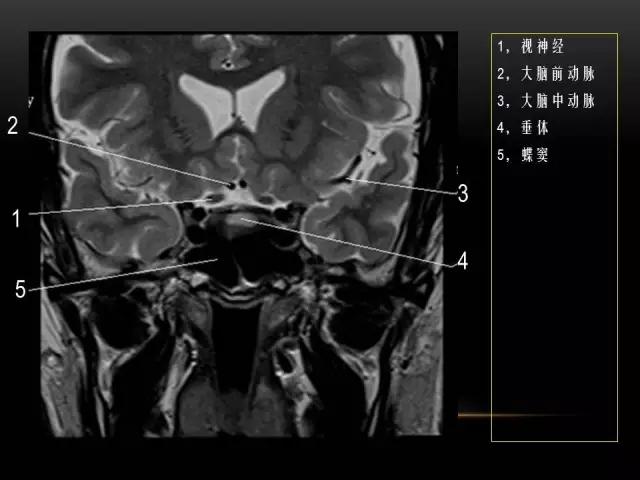

下文是在MRI下眼部及鼻窦的冠状位解剖图谱。